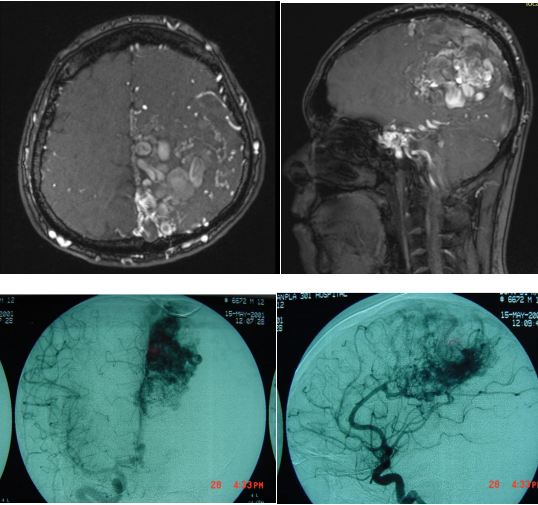

大脑动静脉畸形 (AVM)是大脑中连接动脉和静脉的异常血管的一种混乱。动脉负责将富含氧气的血液从心脏输送到大脑。静脉将缺氧的血液送回肺部和心脏。...